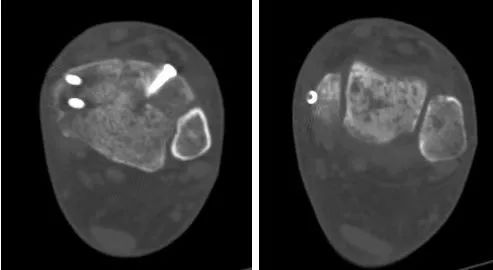

半个月后,王旭教授再次来院,跟九院足踝外科负责人张浩副主任医师通力合作,成功为胡先生实施了“左踝关节镜下探查清理、距腓前韧带修补、内踝截骨、距骨胫骨骨软骨损伤清理、取跟骨植骨术”。手术后影像值得注意的是,对于自体骨的选择,王旭教授巧妙地选择了手术区域临近的跟骨,而非以往的髂骨或膝关节股骨髁,通过控制手术区域和取骨区域的制动,最大程度减少了踝关节及足部的活动影响。在踝关节镜下,通过小切口进行手术,手术时间不长,创伤也不大,出血也很少。仅一周时间,胡先生就出院了。

两个月后,胡先生到医院复查拍片,影像显示原先软骨损伤的位置经植骨后愈合良好,同时患者表示已无明显疼痛。“真没想到痛了这么多年的脚还能恢复得这么好,感谢王教授给我重新找回了健康。再过没多久我应该又可以外出了。”胡先生一边感谢九院团队,一边憧憬着彻底痊愈后的美好生活。

术后影像